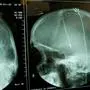

„Ich spüre meine Beine“: Hirnstimulation als Hoffnung für inkomplett Querschnittgelähmte

Die Deep Brain Stimulation (DBS) ist eine etablierte neurochirurgische Technik, bei der Elektroden in bestimmte Regionen des Gehirns implantiert werden. (Sujetbild)

Rückenmarkverletzungen